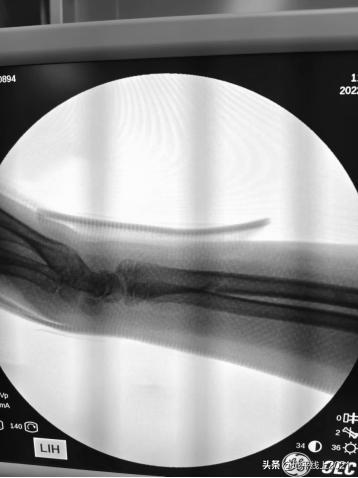

如果真的骨折了,要做手术吗? 儿童不是成人的缩小版,儿童有生长发育和自身的解剖特点——骨膜厚,塑形能力强,而且这类发生在公园和小区里的“事故”,情况通常不会太严重,家长不用太紧张。一提到骨折,许多家长会联想到“做手术”,其实可能 “打石膏” 就够了。下图是一位13岁的男孩,桡骨远端 (可简单理解为“手腕”) 骨折,成角畸形,有医生建议手术治疗,钢板固定。 我们推荐在局部麻醉下,牵引复位,用夹板固定,也取得了很好的效果。 只需一周复诊,调整夹板或者石膏。